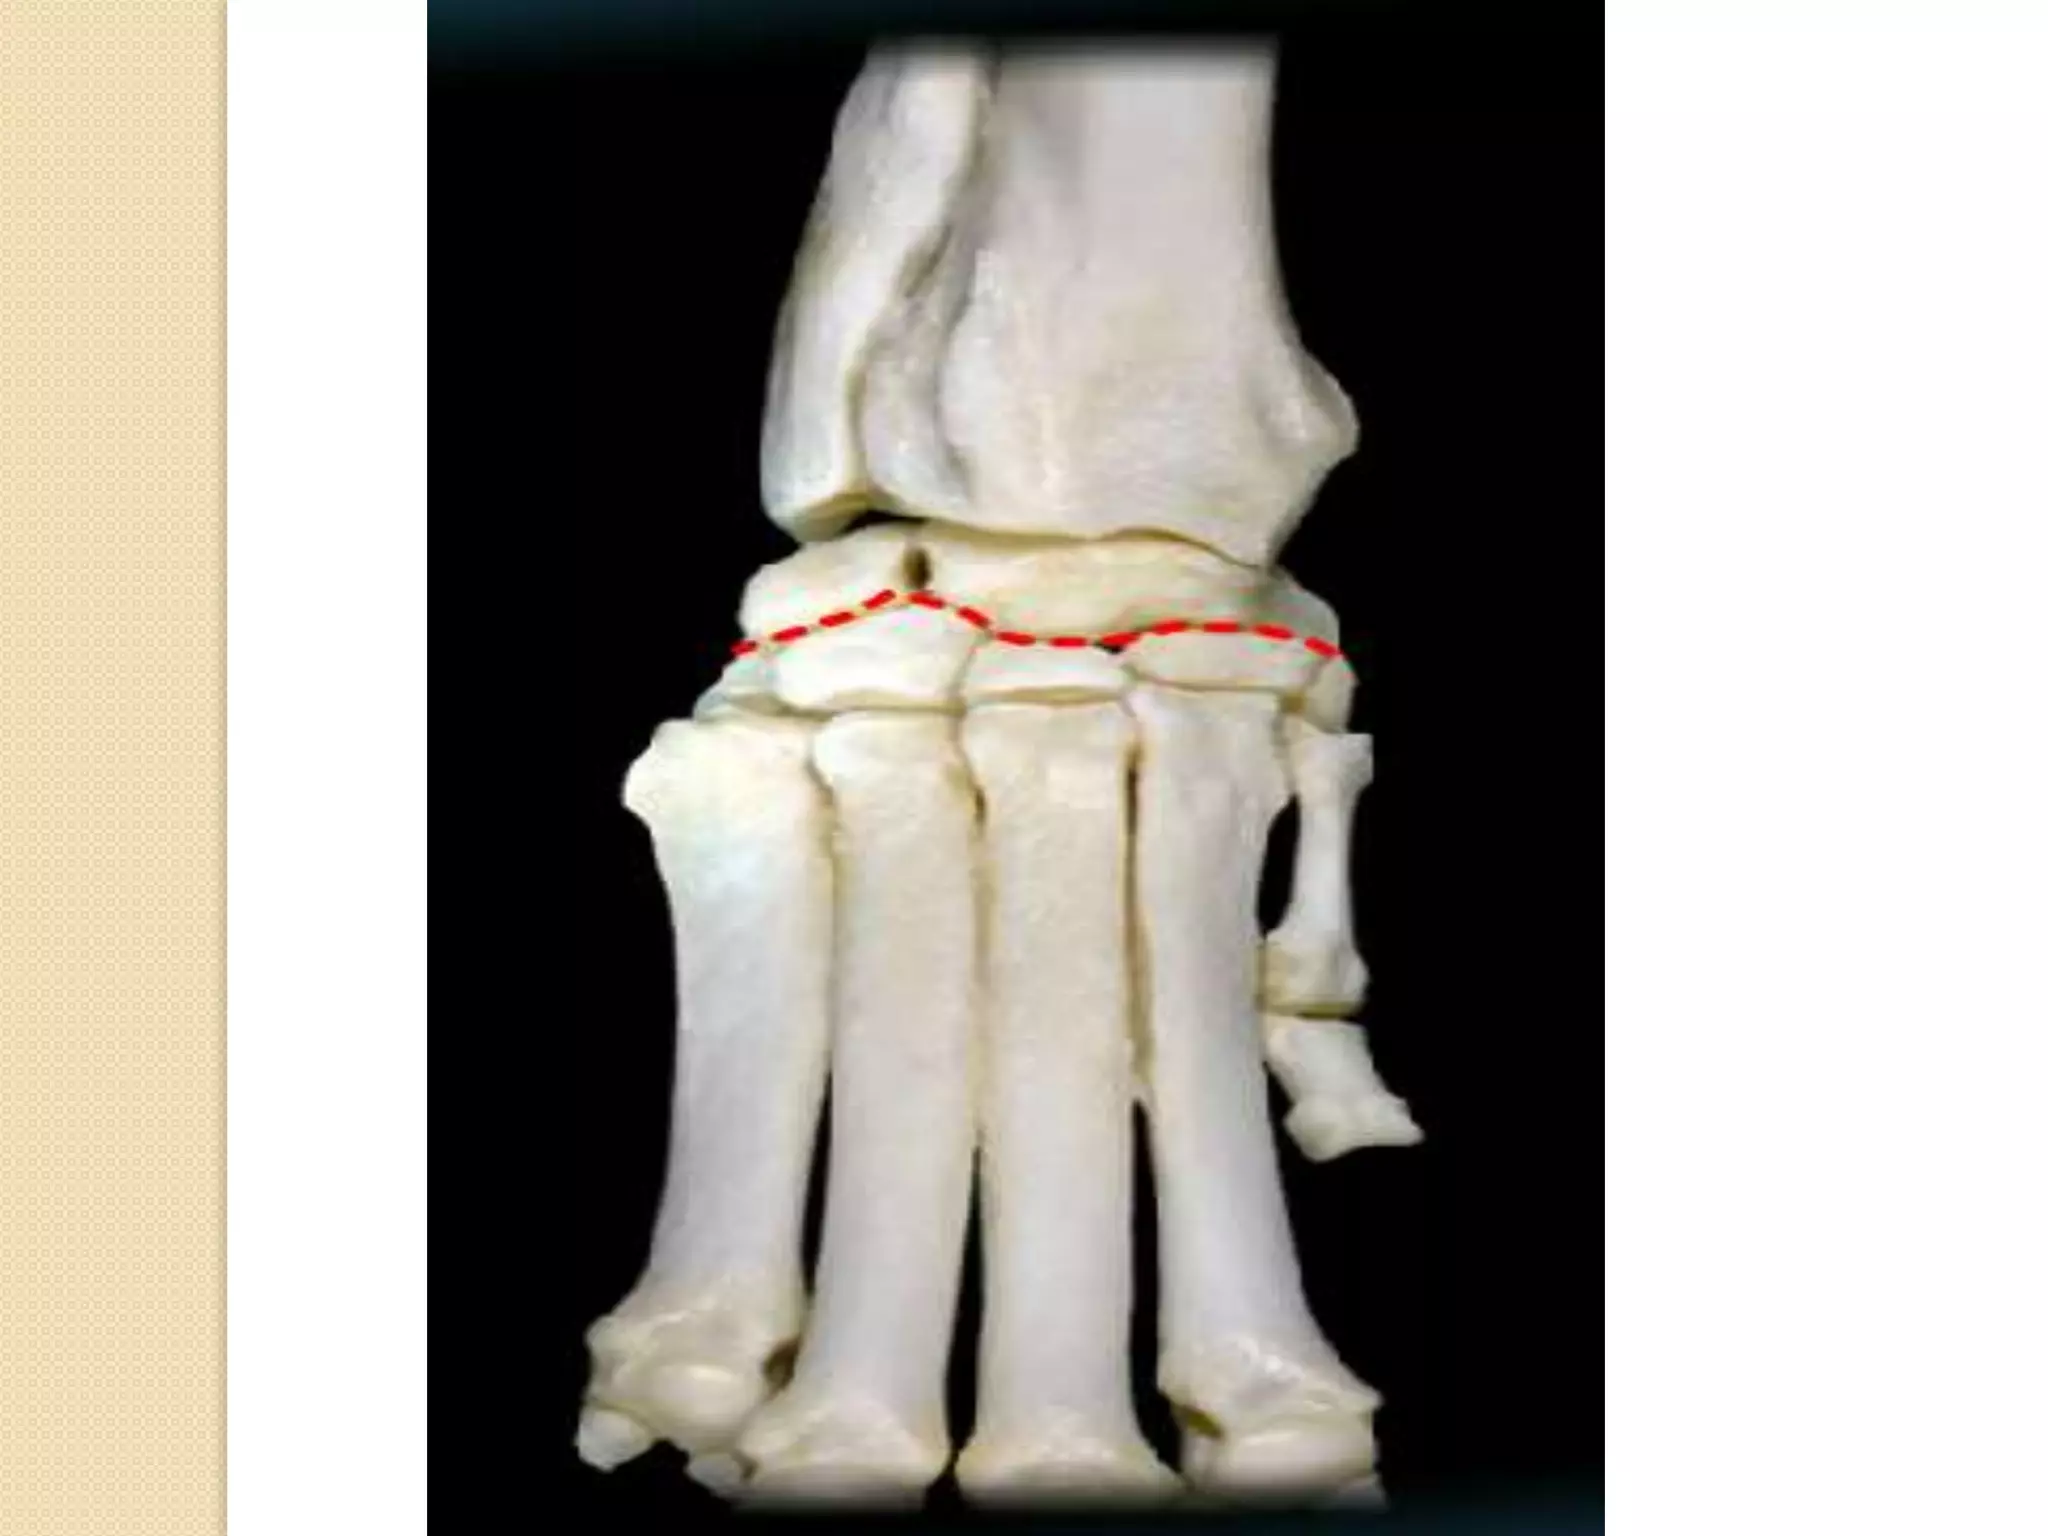

Tarsus , metatarsus and

Tarsus

The cluster of bones are the tarsal bones (A), which

make up the tarsus, or hock. The tibial-tarsal joint is

the same as your ankle.

The calcaneus (B) is the large tarsal bone that makes

up the heel of man. Unfortunately, I could not get a

good view to show that the calcaneus is in the lateral

portion of the hock.

The metatarsal bones are labelled C.

Remember that at the tarsus, cranial becomes dorsal

(E) and caudal becomes plantar (F), just like when

you plant your foot on the ground.

The phalanges (D) are similar to those in the

thoracic limb.